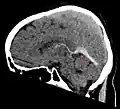

Синус-тромбоз при нативной компьютерной томографии (сагиттальная реконструкция) -